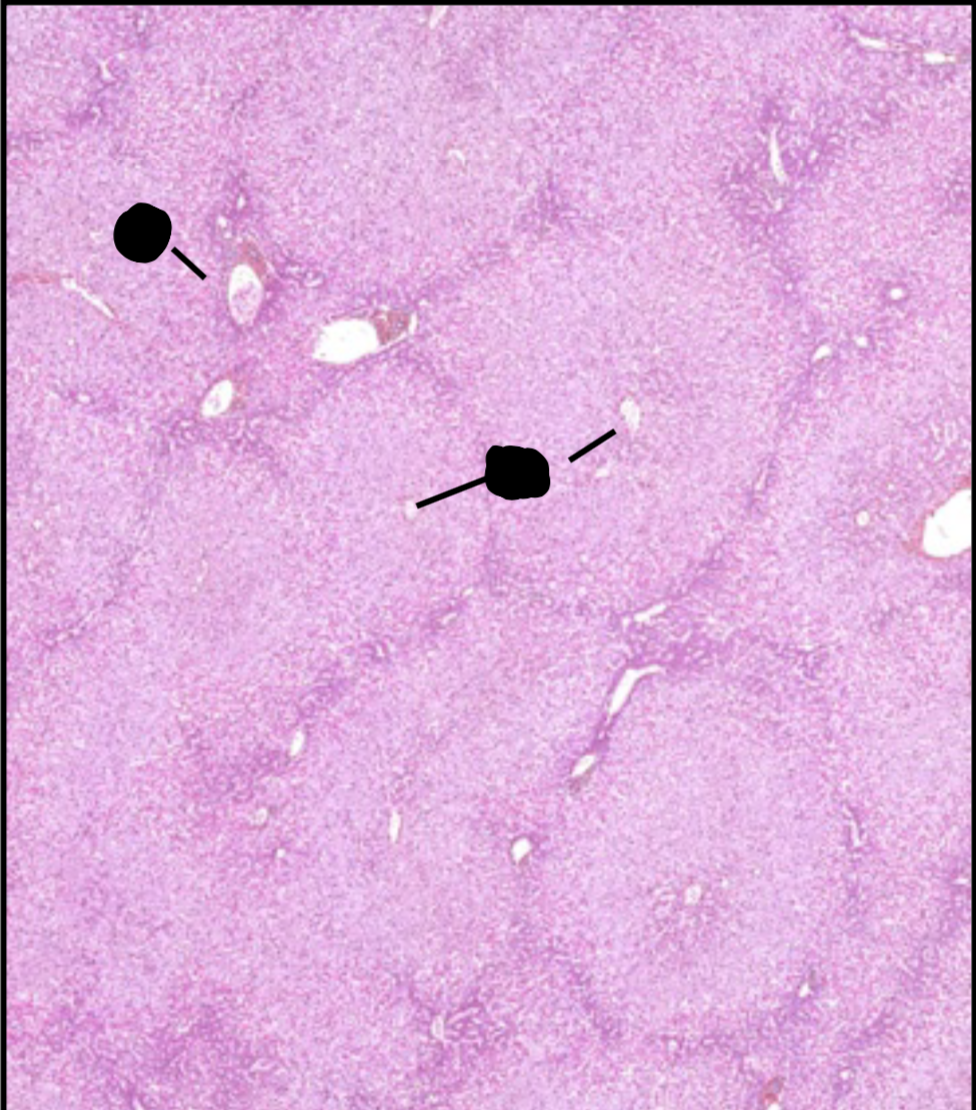

atrophie musculaire